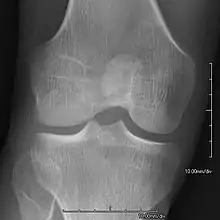

AP radiograph showing a hypoplastic patella in NPS

• Patellar involvement is present in approximately 90% of patients; however, patellar aplasia occurs in only 20%.

• In instances in which the patellae are smaller or luxated, the knees may be unstable.